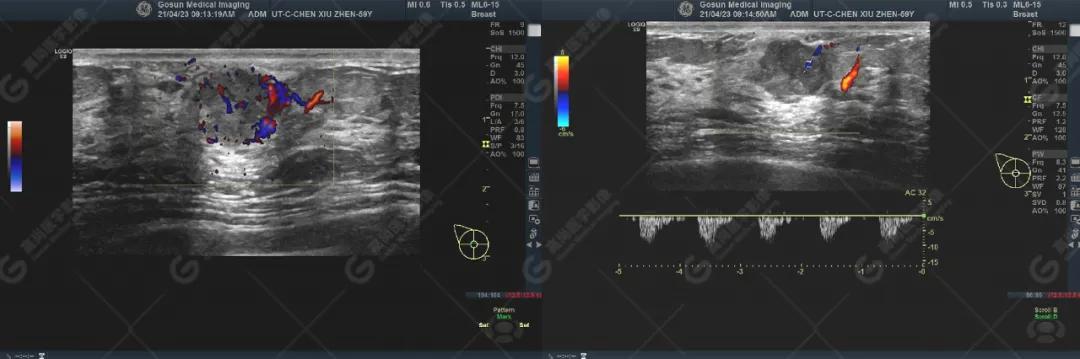

右乳头处见一低回声团块,大小约6mm×7mm,其下方探及一实性低回声团块,大小约17mm×14mm,两者相连,周边与部分导管相连,团块边界欠清,形态不规则,内部可见散在点状强回声,局部见密集点状强回声,CDFI显示周边及内部见丰富血流信号,PW显示较大者Vp=10cm/s,RI=1.0。

超声图像

1) 乳头回声不均匀减低,伴或不伴乳晕区皮肤增厚,增厚乳晕区皮肤与后方脂肪层分界不清。

2) 乳头、乳晕回声异常伴下方大输乳管及远端乳管扩张,管腔内可见低回声,并见多发性微钙化。

3) 乳头、乳晕回声异常病例均能在乳头局部探及丰富血流信号,合并导管内原位癌(ductal carcinoma in situ,DCIS)/非特殊型浸润性癌时可见肿块,肿块形态多不规则,边缘模糊不清,内部呈不均质低回声。肿块内均能探及走行杂乱、扭曲、管径粗细不均匀血管。